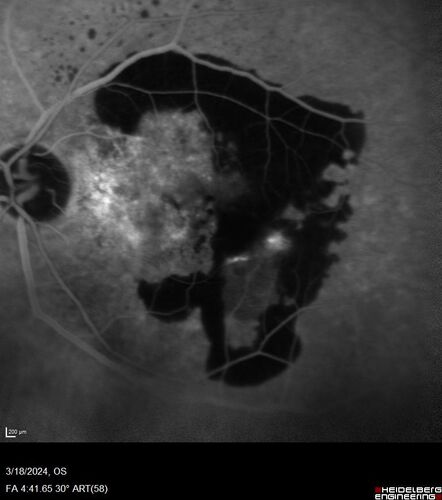

Idiopathic Polypoidal Choroidal Vasculopathy

83 year old man with wet AMD for 12 years resistant to Anti-VEGF therapy but responsive to PDT